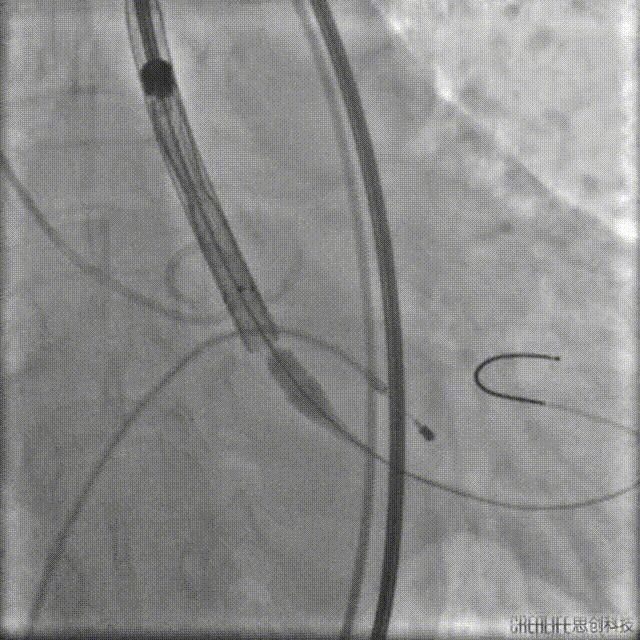

根据术前策略,考虑到瓣上结构,需要近零位释放,精准定位,并至释放工作位,左右重合及左冠切线位评估瓣膜位置良好,最终释放后造影评估少量瓣周漏。

瓣膜定位

瓣膜释放

术后造影